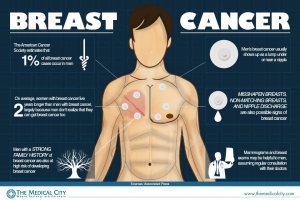

1) Men also get breast cancer. They usually die from it sooner and more often precisely because there is very little “awareness” about males’ getting breast cancer;

image from takboprintipe.wordpress.com

2) A “cuteness” factor of a zillion does NOTHING to help fence-sitters, if there even are any: how could there be, when 1 in 4 women gets breast cancer? Who could be “unaware” of it mystifies me;

from http://www.cancer.org, “Estimated New Cancer Cases* in the US in 2013. Estimated New Cancer Cases* in the US in 2013. Cancer Incidence Rates* by Sex, US, 1975-2009″

3) Waste of time, networking, and energy. I see nothing in any of these “campaign” solicitations that has a call to action, a place to donate for cure research, or ANYTHING but cuteness and “don’t tell the men.”

image from gerson.org

4) BREAST CANCER IS NOT SEXY, just because it afflicts one’s breasts. This year, it’s fruits. Each fruit is supposed to signify the poster’s MARITAL or RELATIONSHIP status. As if the entire campaign weren’t insulting enough to the intelligence of adult women, THIS is the type of device it uses every year. One year, it was some lame statement that was supposed to indicate unusual places that we like to have sex, but really was about where we put our PURSES (I don’t even carry a purse 90% of the time; bad for my back and shoulder). Another year (see above), our bra color or underwear color or other such nonsense.

It’s all supposed to be pseudo-titillating and sexual, which is another gripe I have.

Here is what “feminism” actually means.

With this information in front of you, how could you NOT be a feminist? You can have fun; some things can be cute. I have an excellent sense of humor. But some situations require serious ACTION.